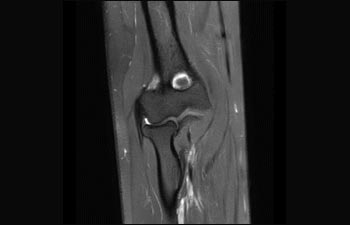

Encuentre la aplicación clínica adecuada a sus necesidades

1De acuerdo con un estudio interno en el que se compara el flujo de trabajo con el equipo de RM Achieva. 2 ComforTone estará disponible con Prodiva 1.5T en el cuarto trimestre de 2017 3 De acuerdo con un estudio interno donde se compara el flujo de trabajo en una combinación de aplicaciones cerebrales, musculoesqueléticas, de columna y de cuerpo con el equipo de RM Achieva 4 La operación normal se define como una adquisición típica realizada con suministro continuo de electricidad, así como de refrigeración del imán, sin incluir las actividades de servicio 5 En función del contrato y de la disponibilidad local 6 Con "otros equipos de RM" nos referimos a equipos de RM de 1,5 T de 60 cm para exámenes de cuerpo entero